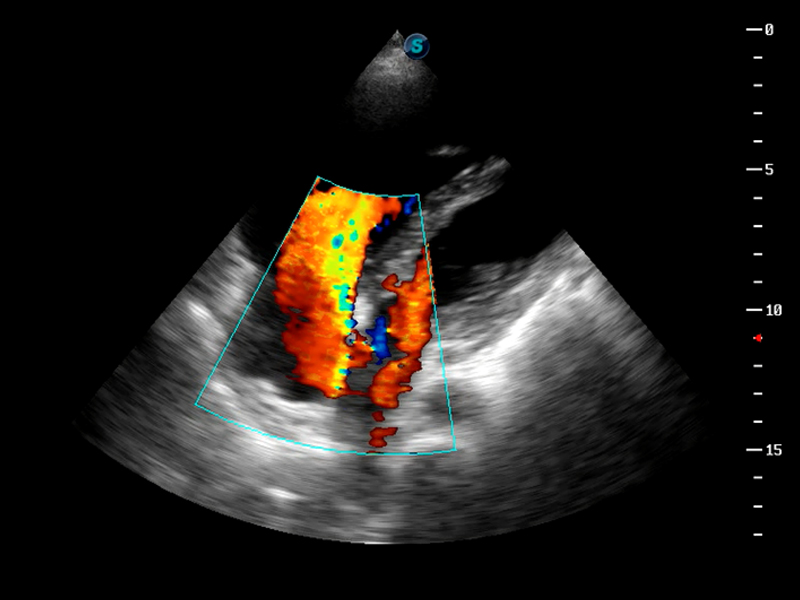

TDI组织多普勒成像